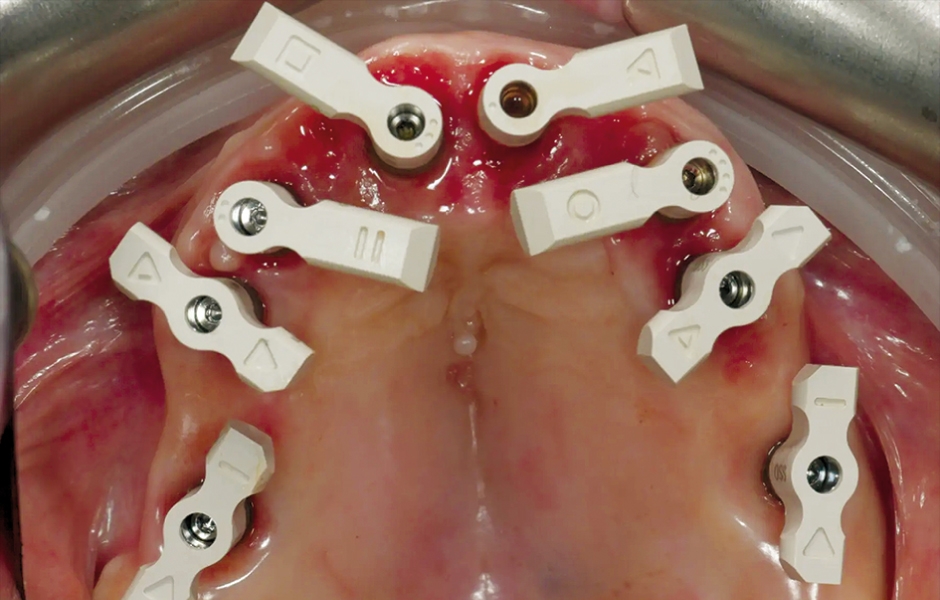

V den operace byla aplikována lokální anestezie a první chirurgická šablona byla stabilizována na zbývajících zubech k přípravě pěti fixačních pinů. Poškozené zuby byly extrahovány a druhá chirurgická šablona byla upevněna v připravených místech. Osm implantátů (Osstem TSIII SOI, Osstem Implant) bylo umístěno – pět do čerstvých extrakčních alveolů a tři do dříve zahojených oblastí. Všechny implantace proběhly plně navigovaně pomocí chirurgické šablony bez kovových pouzder a s dedikovanou chirurgickou sadou (OneGuide KIT, Osstem Implant; obr. 8). [11] Jeden implantát vyžadoval krestální sinus lift, který byl proveden plně navigovaným přístupem (OneCAS KIT, Osstem Implant; obr. 9). Xenogenní kostní materiál (A-Oss, Osstem Implant) byl použit k vyplnění extrakčních alveolů a dutiny sinu. [12] Na všechny implantáty byly okamžitě nasazeny multi-unit abutmenty a dočasné abutmenty (Osstem Implant) podle konceptu „one abutment, one time“. [13] Předem připravená dočasná protetika na bázi PMMA s kovovou výztuhou byla vložena a ihned fixována v ústech. V ordinaci byly provedeny úpravy pro dosažení správné okluze (obr. 10–12). Pacient obdržel pooperační instrukce a medikaci.

Obr. 6: Chirurgická šablona bez kovových pouzder pro přípravu fixačních pinů.

Obr. 7: Chirurgická šablona bez kovových pouzder pro plně navigovanou implantaci.

Obr. 8: Zavádění implantátu pomocí sady OneGuide KIT.